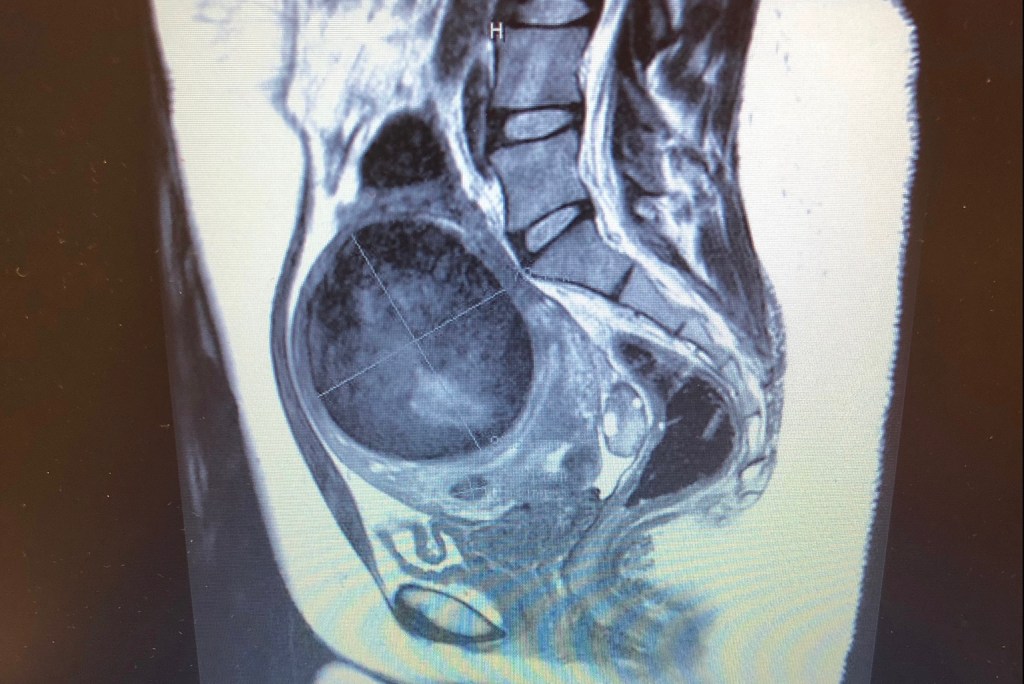

It wasn’t until after I lost Ezra that the doctors placed the blame on the fibroid. It wasn’t until I found a new doctor (based off a recommendation) that an MRI was ordered. This is where I learned there were six fibroids. It wasn’t until another doctor saw the MRI where we finally figured out what happened. The fibroid squished my uterus and pushed my Ezra out.